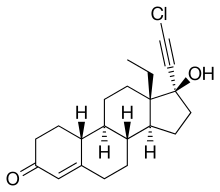

Chloroethynylnorgestrel (developmental code name WY-4355) is a steroidal progestin of the 19-nortestosterone group related to norgestrel that was investigated as an oral contraceptive in the 1970s but was never marketed.[1][2][3][4]

| Other names | Chloroethynyl norgestrel; WY-4355; 17α-Chloroethynyl-13β-ethylgon-4-en-17β-ol-3-one; 17α-Chloroethynyl-18-methylestr-4-en-17β-ol-3-one; 17α-Chloroethynyl-18-methyl-19-nortestosterone |

| Formula | C21H27ClO2 |

| Molar mass | 346.90 g·mol−1 |